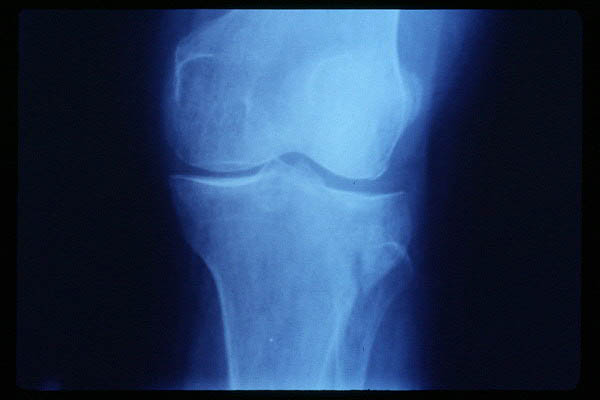

APR Gonartrosis